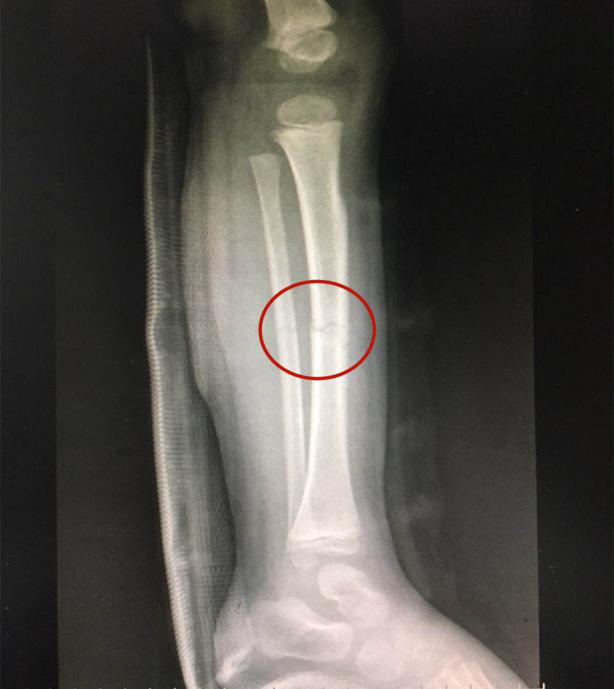

接诊的泸州市中医医院骨伤一科副主任中医师李孟泽查看了患儿之前的X光片及左下肢情况,发现其骨折移位较大(骨折处弯曲呈30度角以上),导致左下肢中段严重畸形。

复位后,经再次照X光显示,患儿左下肢胫腓骨断端紧密对合,外观畸形得以纠正,手法复位治疗非常成功。

手法复位前X片显示胫腓骨断端,左下肢中段严重畸形

手法复位后X片显示胫腓骨断端严密对合,左下肢中段畸形纠正